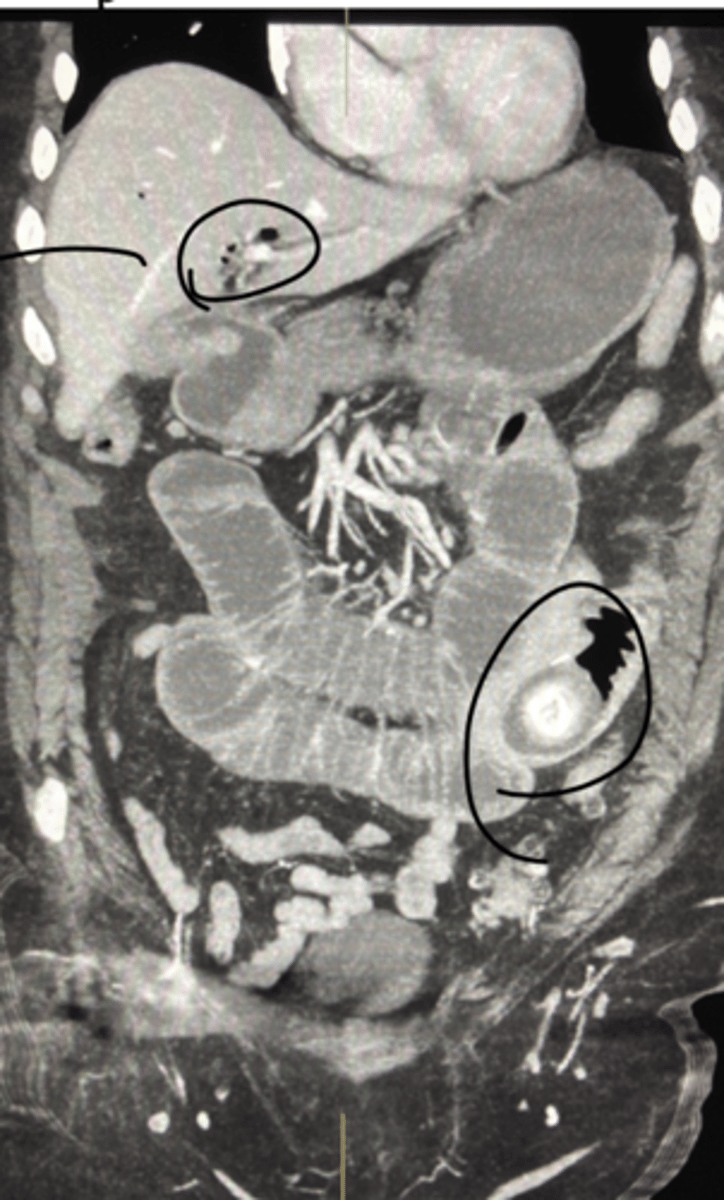

Chronic Pancreatitis

Define Condition:

Prolonged pancreatic inflammation --> Irreversible destruction of exocrine pancreas + Fibrosis

-Hx:

> MCC = Chronic Excess EtOH use

> May be Idiopathic

> 25% have GENETIC PREDISPOSITION = Cystic Fibrosis, SPINK1 (encodes trypsin inhibitor) mutation

> Repeated episodes of Acute Pancreatitis

> More in MALES

-Path: Chronic Pancreatic Injury --> Inflammatory Mediators (TGF-Beta & PDGF) ==> Activation/Proliferation of Pancreatic Stellate Cells --> More Periacinar Myofibroblasts ==> Collagen Deposition & Fibrosis

-Sx/PE:

> Chronic/recurrent Abd Pain

> Steatorrhea & Malabsorption

>> Pancreatic Burnout of enzymes (Pancreatic Insufficiency) --> Less Proteases/Lipases --> Can't Absorb Fat ==> Fat Soluble Vitamin Deficiencies

-Dx:

> Imaging (CT): Multiple pancreatic calcifications

> Gross:

>> FIRM w/ dilated ducts

>> Calcified concretions

> Biopsy:

>> Parenchymal fibrosis

>> Smaller size/number of acini --> Acinar Loss

>> Variable dilation of ducts +/- Inspissated concretions

>> Chronic Inflammation

>> Eventual loss of islet of langerhans

-Tx:

-Prog:

> Secondary D2M (loss of Islet of Langerhans)

> Pancreatic Insuffiency

> Pancreatic Pseudocysts

> Increased risk of Pancreatic Carcinoma